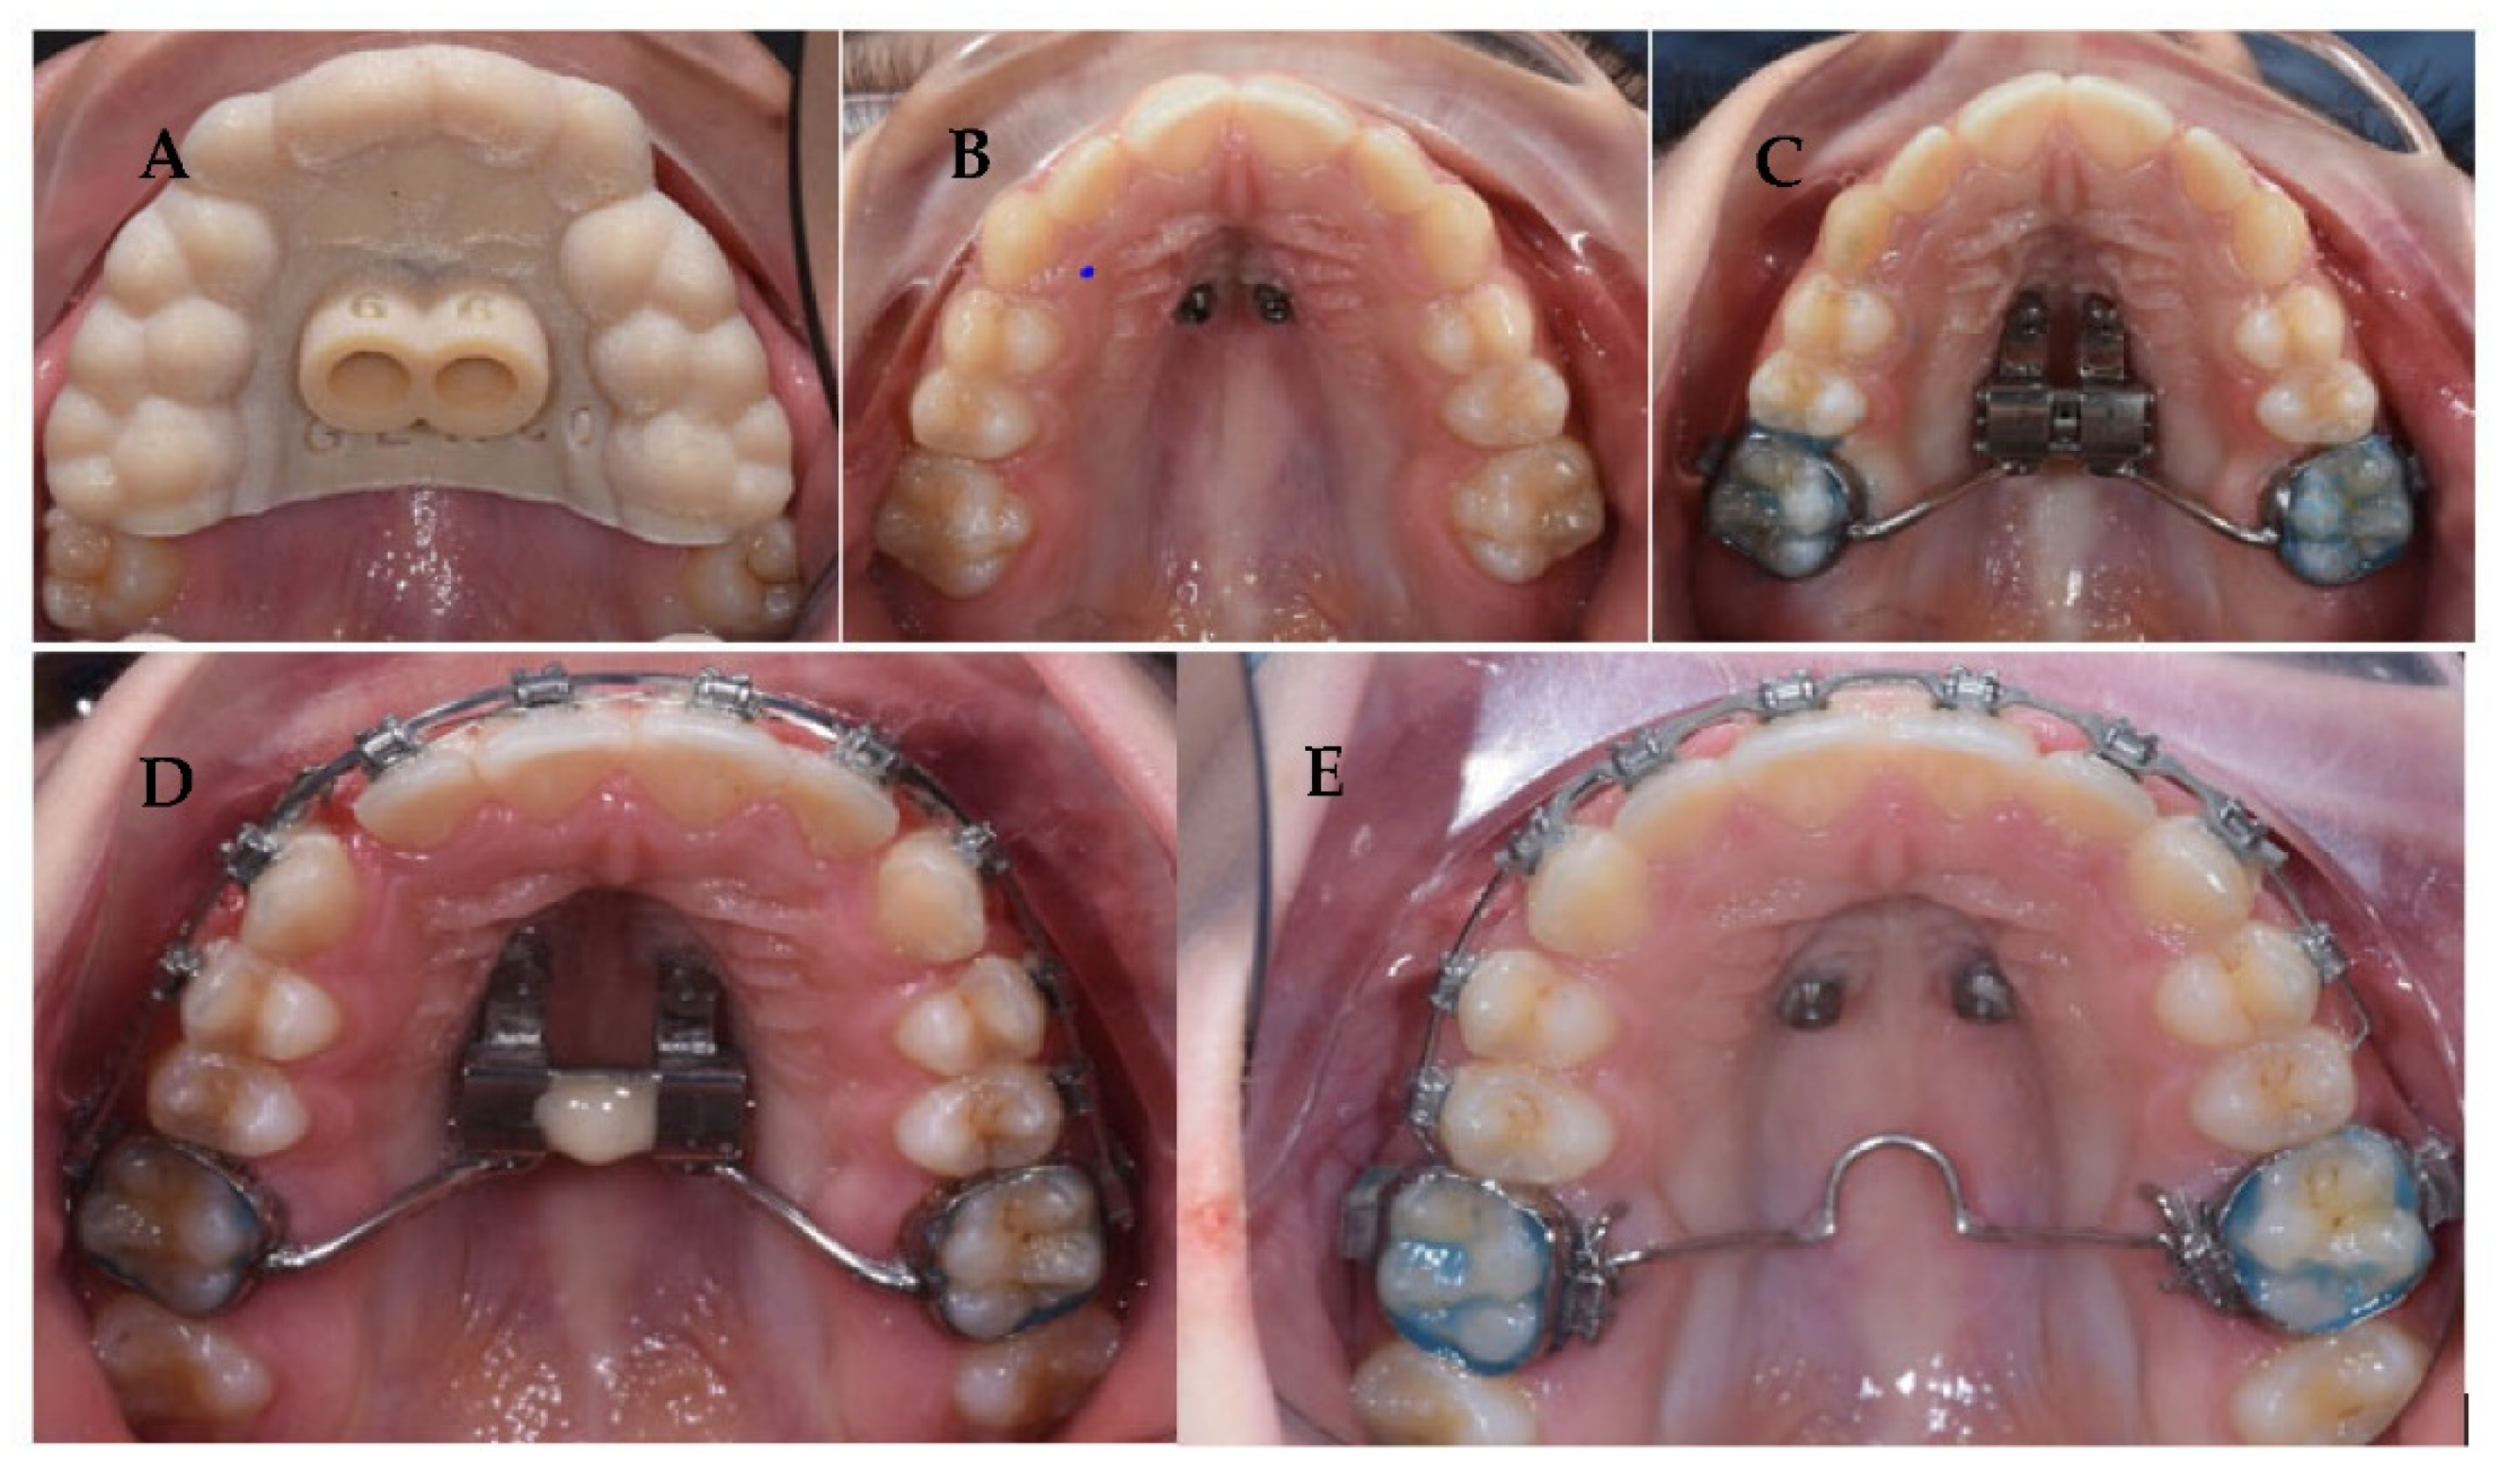

4. Case Report

4.1. Etiology and Diagnosis

4.2. Treatment Objectives

4.3. Treatment Strategy

4.4. Treatment Progress